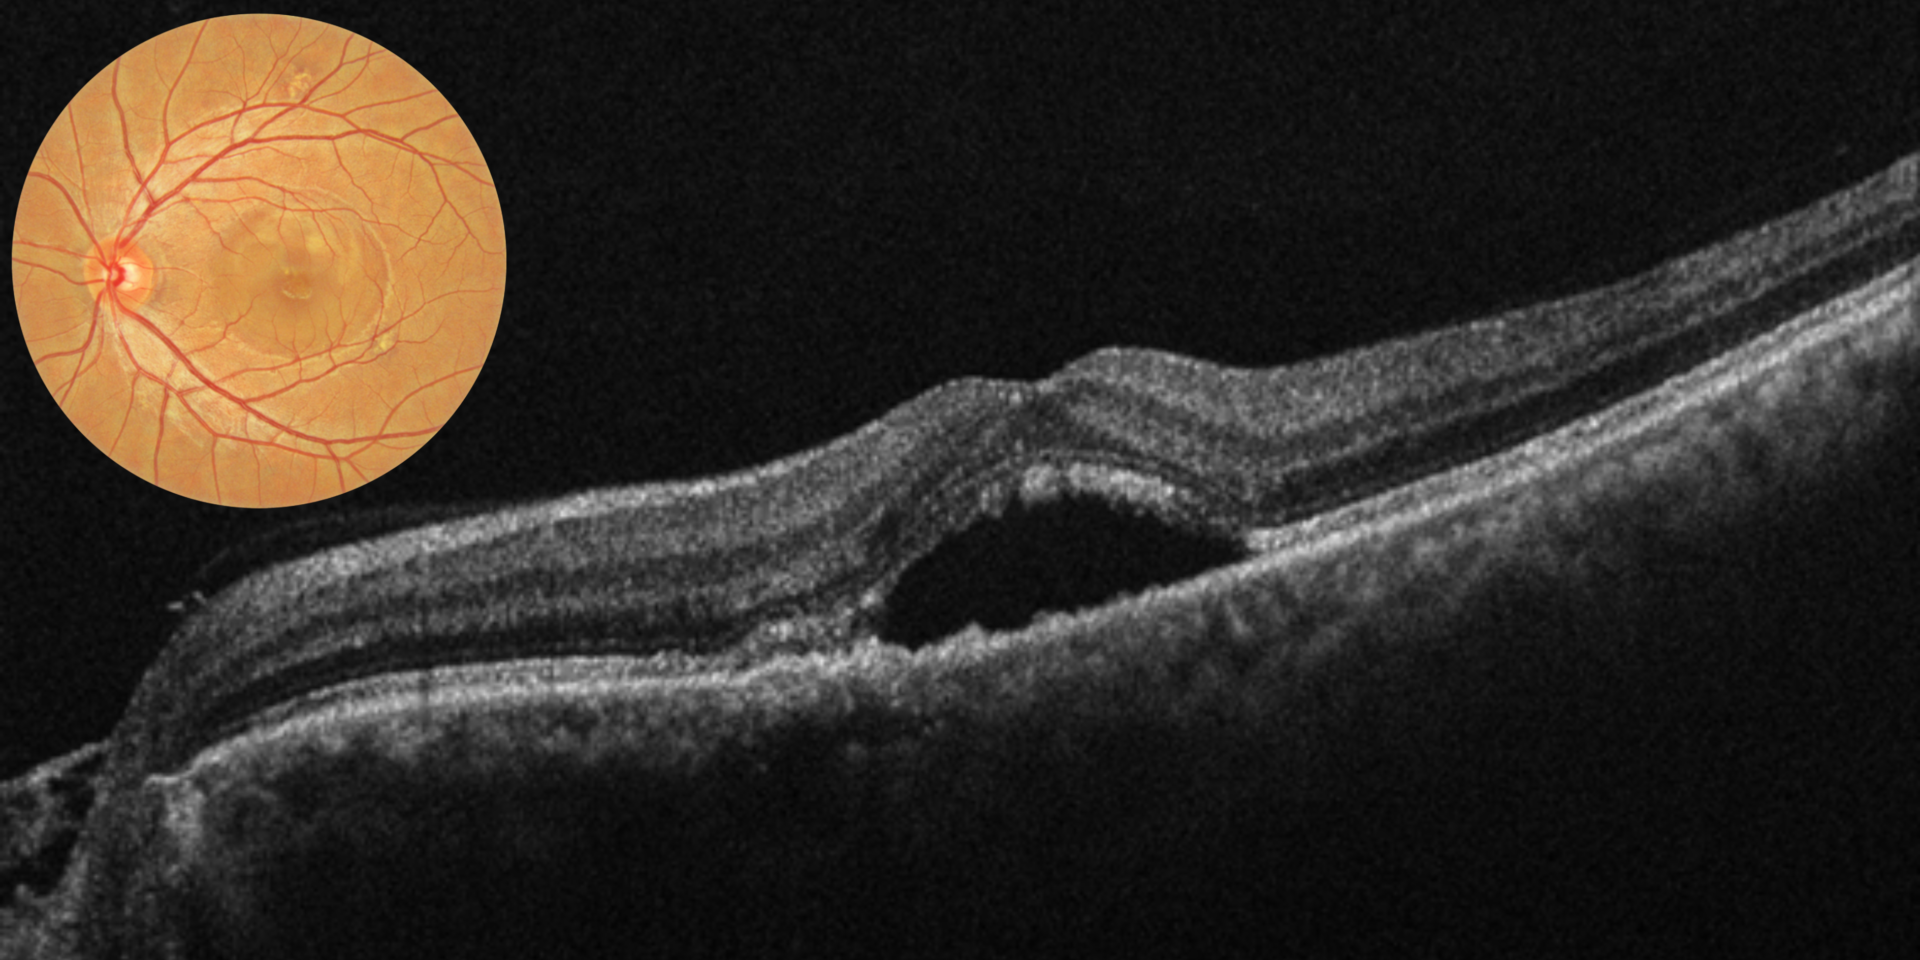

Macular hole

Epiretinal membrane

Central serous chorioretinopathy (CSCR)

Optical Coherence Tomography (OCT)

Fundus Photography